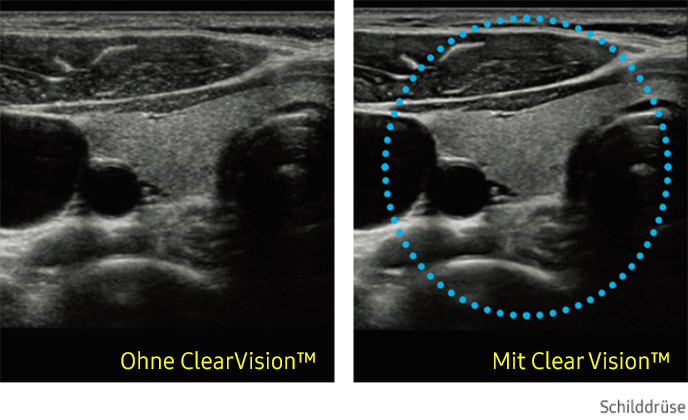

ClearVision

Der Rauschunterdrückungsfilter verbessert die Kantendarstellung und schafft schärfere 2D-Bilder für eine optimierte Diagnoseleistung. Die Integration dieser spezialisierten Samsung-Technologie führt zu einer bemerkenswerten Verbesserung der Bildqualität. Darüber hinaus bietet ClearVision anwendungsspezifische Optimierungsmöglichkeiten und eine erweiterte zeitliche Auflösung im Live-Scan-Modus.

Ultraschallbild Schilddrüse links ohne ClearVision und rechts mit ClearVision von Samsung. Ultraschallbild Schilddrüse links ohne ClearVision und rechts mit ClearVision von Samsung. Ultraschallbild Schilddrüse links ohne ClearVision und rechts mit ClearVision von Samsung. Ultraschallbild Schilddrüse links ohne ClearVision und rechts mit ClearVision von Samsung.